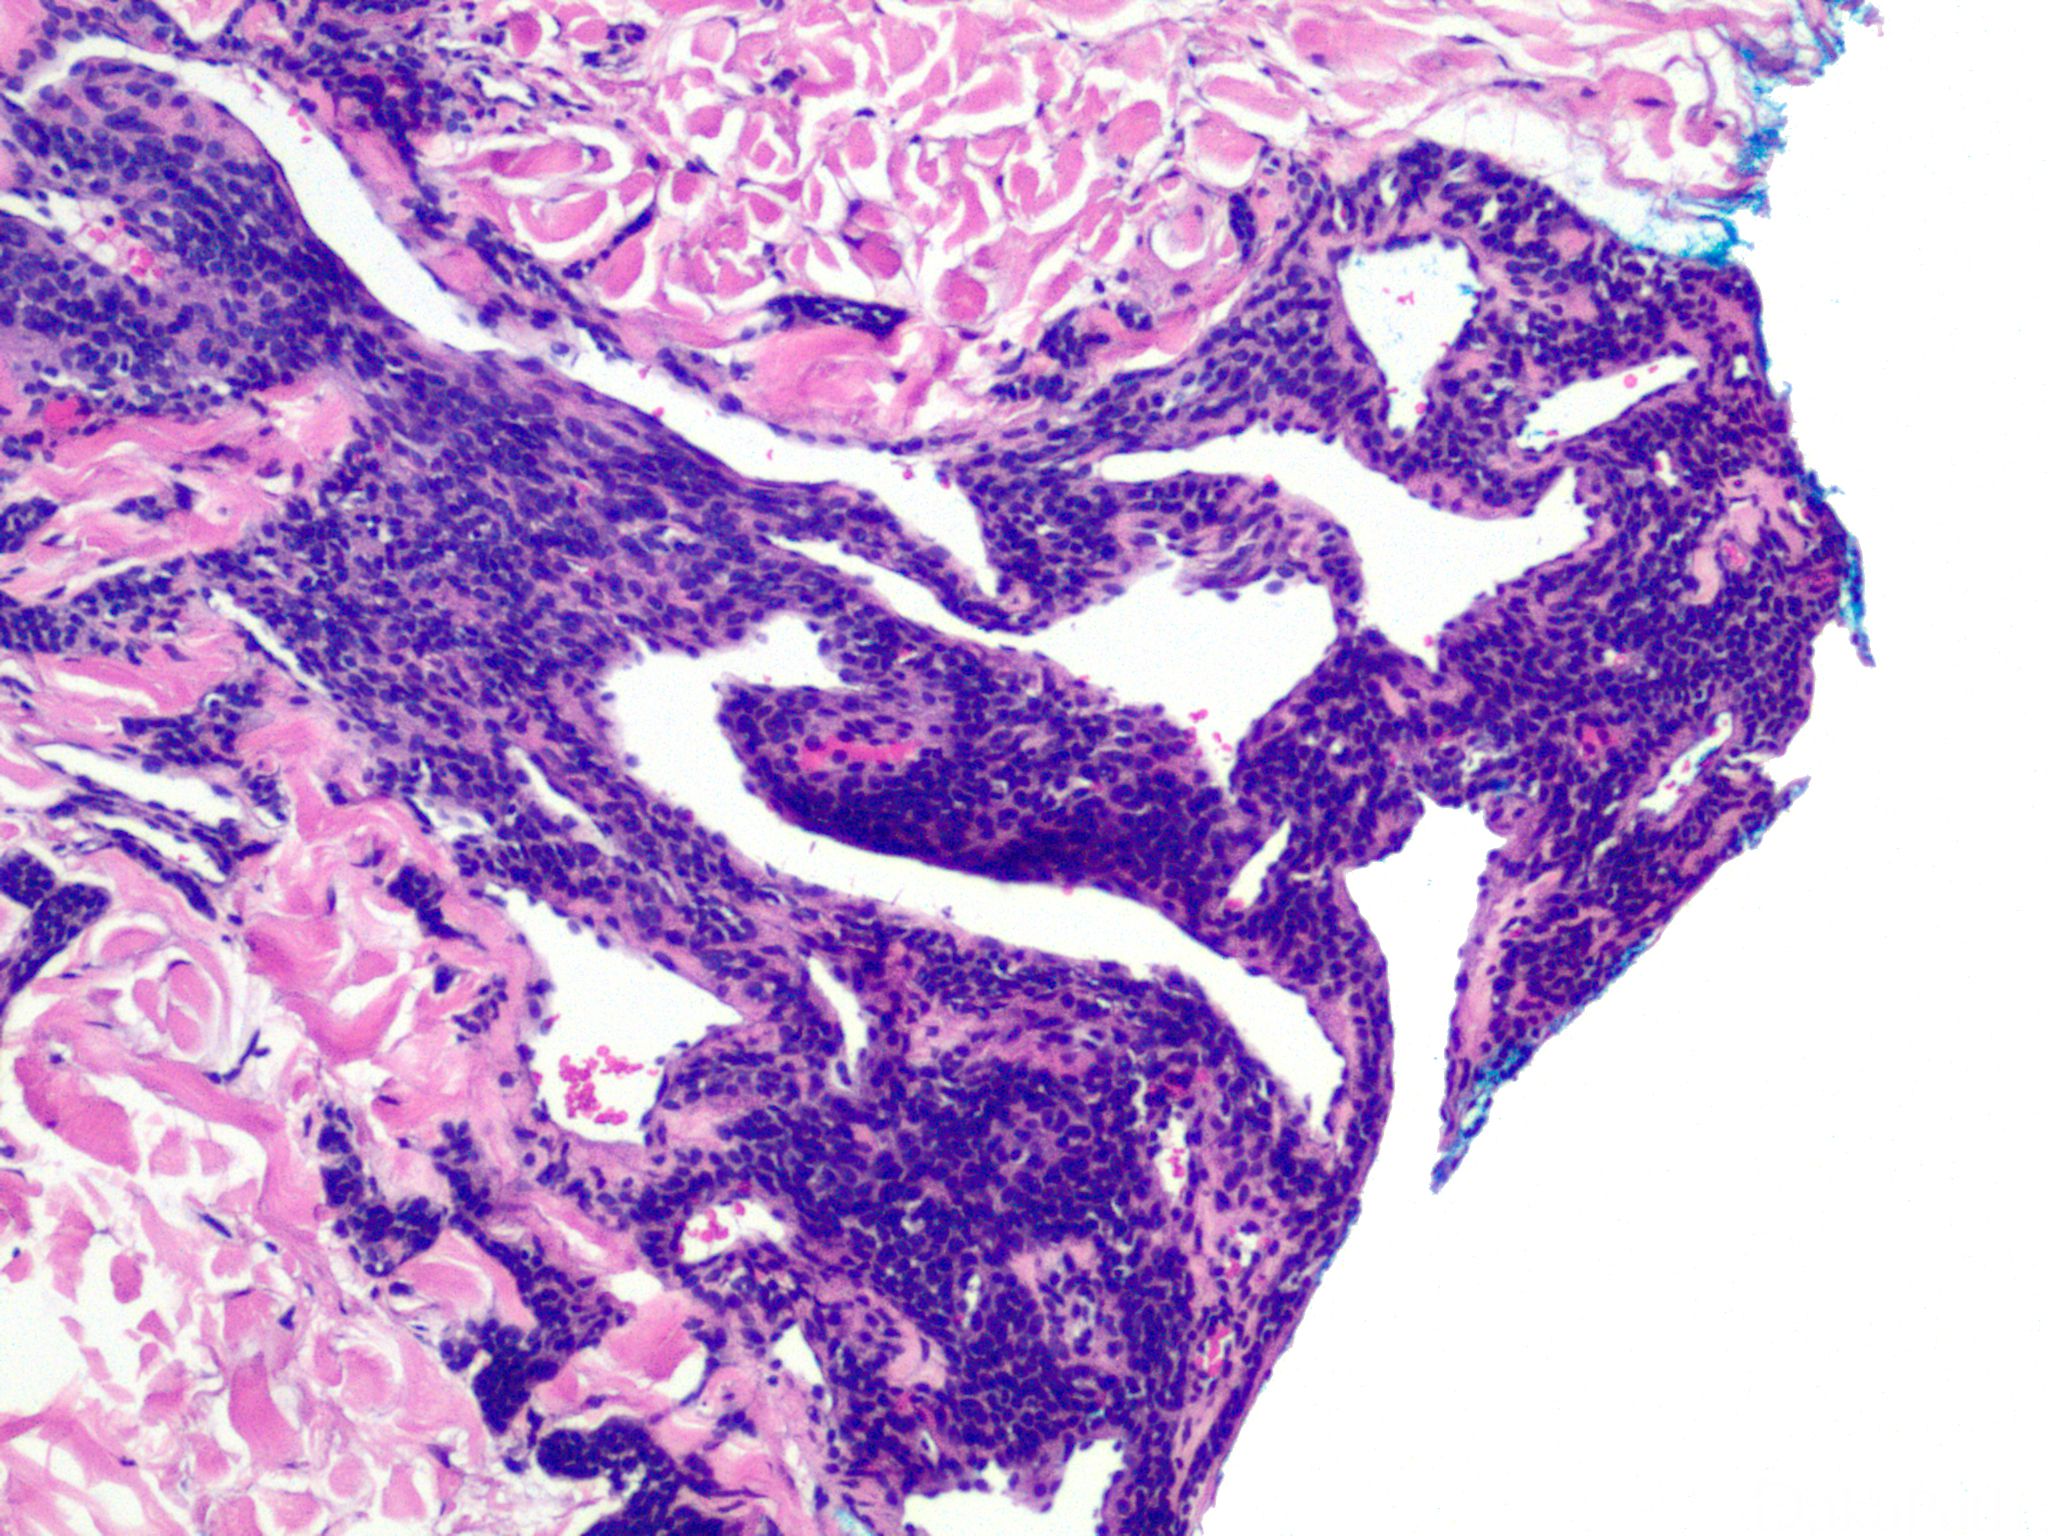

血管球瘤

glomus tumor